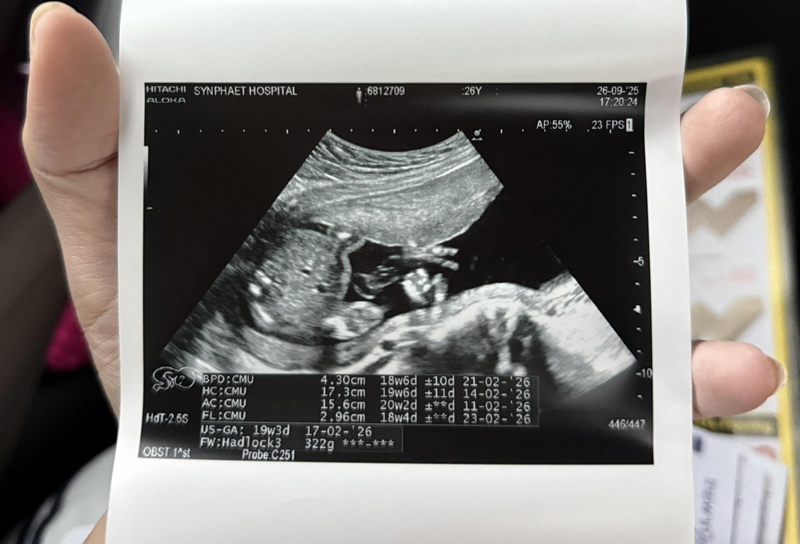

ครูเบียร์ นุติญา ได้เผยอาการป่วยผ่านแคปชั่นว่า "จากเหตุการณ์เมื่อสามวันที่แล้วเบียร์รู้สึกตุบ ๆ ในท้อง รู้สึกแปลก ๆ และได้ถามทุกคนว่าอาการตุบ ๆ อยู่ตรงท้องนี่คืออาการของลูกดิ้นหรือเปล่า เพราะเราไม่เคยท้องมาก่อน ทุกคนบอกว่าน่าจะลูกดิ้น แต่เบียร์ก็รู้สึกผิดปกติอยู่ดี เบียร์เลยได้ไปหาคุณหมอ

เนื่องจากตอนนั้นมีอาการปวดหัว ปวดเบ้าตาร่วมด้วย เพราะกินยาพาราก็ไม่หาย วันต่อมาก็เป็นอีกและอาการปวดหน่วงท้องยังมีอยู่ ก็เลยตัดสินใจไปหาคุณหมอที่ฝากครรภ์ แล้วคุณหมอก็ได้อัลตราซาวด์

ได้ผลสรุปว่า "มดลูกบีบตัว" ซึ่งมันไม่ควรที่จะเกิดขึ้นกับคนท้องระยะครรภ์ประมาณ 4-5 เดือน แต่มันควรจะเกิดขึ้นสำหรับคนท้องอายุครรภ์ 7-8 เดือน คุณหมอเลยให้งดให้เดินทางไกล งดยืนนาน ๆ งดการขยับเร็ว และให้ใส่ผ้าพยุงครรภ์ไว้ เนื่องจากกลัวว่าจะมีผลกระทบต่อเบบี๋ในครรภ์ เพราะอาจจะเสี่ยงคลอดก่อนกำหนด แล้วคุณหมอก็ให้ยามาทานแล้วค่ะ แต่อาการยังไม่หาย.."